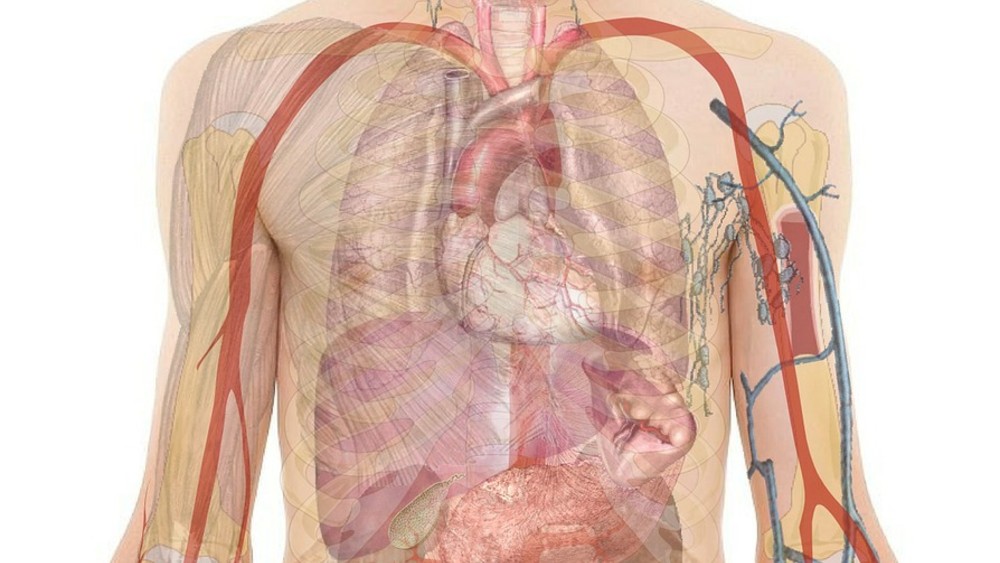

Foto: Pixabay/GeraltU slučaju neke spoljašnje povrede, poput posekotine, povređeni obično koriste flaster ili zavoj, ali je situacija komplikovanija kada su u pitanju unutrašnje povrede.

Tako lekari koji tretiraju povrede digestivnog trakta ne mogu da primenjuju ovakve metode, ali bi tim eksperata sa Harvard univerziteta uskoro mogao da reši i taj problem, prenosi Pcpress.rs.

Naime, naučnici sa ovog univerziteta kreirali su gel od bakterija iz ljudskog tela koji sadrži i mikro-vlakna koja mogu da ojačaju povređeno tkivo. Radi se o izmenjenoj bakteriji E. Coli koja se inače nalazi u ljudskom organizmu, a radi se o varijanti koja je modifikovana tako da pacijente ne može da dovede u opasnost.

Bakterija se proizvodi u laboratorijskim uslovima i može da se doda u sprejeve kojima bi se tretirale unutrašnje povrede. Hidrogel je slične gustine kao sluz koju proizvodi ljudski organizam, i kreatori tvrde da može precizno da cilja povređenu oblast.

Tim koji je kreirao novi gel proizvod opisuje kao način na koji „telo može da se prevari“, a kako bi što pre započelo prirodni proces zaceljenja. Rezultat je takozvani „zavoj u obliku spreja“, koji za razliku od većine materijala može da izdrži uslove u ljudskom digestivnom traktu, te može da potraje od jednog do pet dana, i tako ubrza izlečenje.